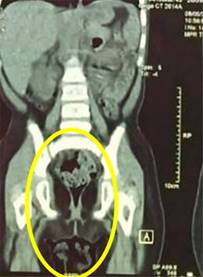

La paciente se hospitaliza para realizar tomografía; el estudio confirmó la presencia de una masa intravesical de 4 × 3 cm de diámetro y 5 × 3 cm de longitud, con lesiones hiperdensas con centros hipodensos (Figura 3); además se observaron ganglios linfáticos inguinales bilaterales de aspecto reactivo e hidronefrosis bilateral grado 2. Pero sin evidenciar metástasis a distancia (Figura 4).

Figura 3: Tomografía simple de abdomen, corte coronal. Se observa masa a nivel vesical, multilobulada con contorno hiperdenso y centro hipodenso múltiples, de aproximadamente 4 × 5 cm.

Figura 4: Tomografía simple de abdomen con corte coronal con masa a nivel vesical, pero sin metástasis.